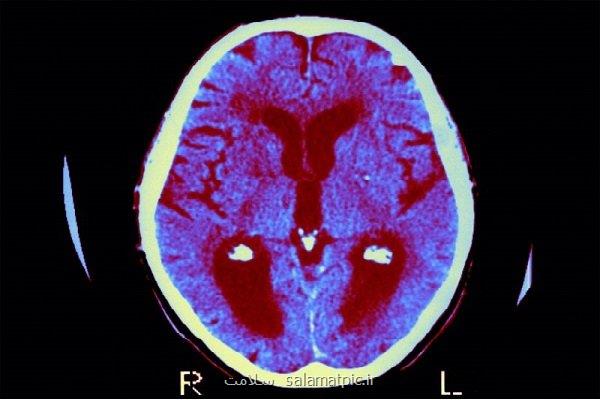

به گزارش سلامت، یک مطالعه جدید می گوید هورمون درمانی برای یائسگی امکان دارد بتواند حافظه را تقویت کند.

به گزارش سلامت به نقل از مهر به نقل از مدیسن نت، علاوه بر این، محققان دریافتند که نوع خاص هورمون درمانی که یک زن در دوران یائسگی و بعد از آن استفاده می نماید، می تواند اثرات متفاوتی بر حافظه او داشته باشد.

گالیا در یک بیانیه خبری اظهار داشت: «این مطالعه نشان داده است که نوع درمان استرادیول مورد استفاده امکان دارد بر عملکرد شناختی در انواع مختلف حافظه تاثیر متفاوتی داشته باشد. درک این ارتباطات می تواند به عرضه رویکرد های متناسب تر برای حفظ سلامت مغز بعد از یائسگی کمک نماید.»